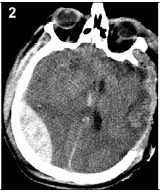

20160503094709

20160503094717

20160503094723

20160503094729